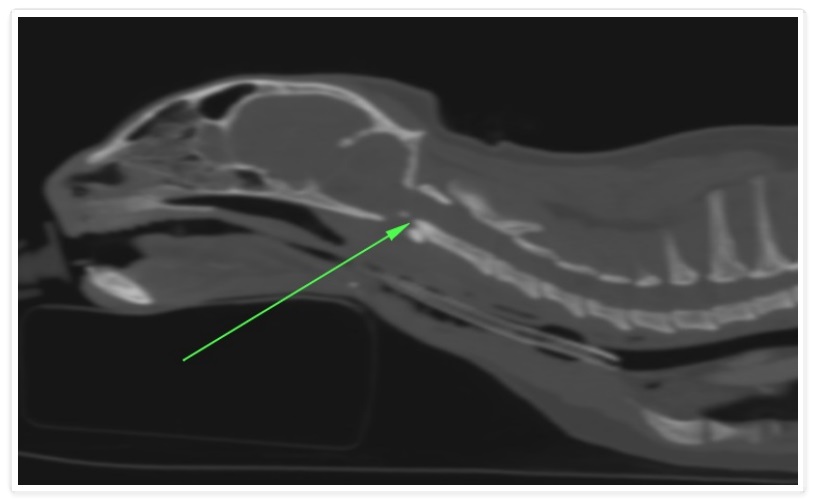

L'Ospedale degli Animali offre il servizio di Ortopedia Veterinaria, attivo 24 ore su 24 e 7 giorni su 7. Siamo in grado di eseguire visite speiaclistiche ortopediche, studi radiografici, ecografie muscolo-scheletriche e studi tomografici ortopedici.

Il primo step è sempre rappresentato dalla visita clinica specialistica, che comprende una approfondita raccolta della storia clinica ed una attenta valutazione dell'animale.

Al momento della visita il medico potrà richiedere eventuali approfondimenti diagnostici: studi radiografici, esami del sangue, ecografie muscolo-scheletriche o esame tac.